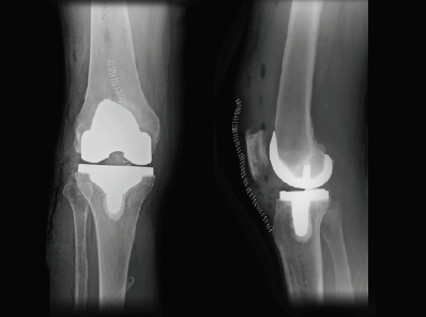

Total knee replacement (TKR) is a significant surgical procedure aimed at relieving pain and restoring mobility for those suffering from arthritic conditions. While many patients experience a profound improvement in quality of life post-surgery, it’s essential to understand the pain associated with the procedure and the recovery process, including effective pain management strategies. Patients can be surprised by the level of early discomfort if they are not given appropriate education.